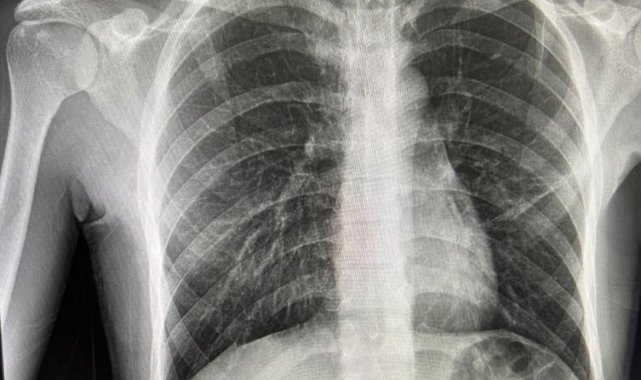

Bayburt'ta nefes darlığı şikayetiyle acil servise başvuran ve daha önce de spontan pnömotoraks (akciğer sönmesi) öyküsü bulunan bir hasta, Göğüs Cerrahisi Uzmanı Op. Dr. Halil Kolcu tarafından yapılan başarılı müdahaleyle sağlığına kavuştu.

Yeniden akciğer sönmesi tanısı konulan hastaya, Op. Dr. Halil Kolcu tarafından 3 santimetrelik tek kesiyle kapalı olarak cerrahi tedavi uygulandı. Bilinci açık ve uyanık bir şekilde işlem uygulanan hasta, başarılı geçen operasyonun ardından aynı gün içerisinde taburcu edildi. Yapılan cerrahi müdahale ile hastanın sağlığına kavuştuğu öğrenildi.